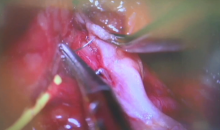

This video demonstrates surgical repair of the phrenic nerve in a patient diagnosed with right diaphragm paralysis resulting from a prior neck surgery. Intraoperative chest fluoroscopy is performed to confirm the diagnosis and assess for immediate results following phrenic nerve reconstruction. The surgical approach begins with an incision in the area of the supraclavicular fossa. Key landmarks to identify proximity to the phrenic nerve include the posterior border of the sternocleidomastoid muscle medially, the brachial plexus laterally, and the anterior scalene muscle, upon which the phrenic nerve courses. A comprehensive microscopic neurolysis of the phrenic nerve and upper cervical roots is performed.

After the phrenic nerve is identified, intraoperative nerve threshold testing is used to evaluate any remaining electrical activity prior to intervention. Careful neurolysis or nerve decompression is performed to dissect away adhesions, sites of vascular compression, and areas of fibrosis along the nerve sheath, in an attempt to restore nerve conductivity. Electrodiagnostic testing is repeated throughout the procedure to objectively assess for immediate improvement.

The sural nerve is then sewn into the phrenic nerve, proximal and distal to the visualized defect. During this bypass, the phrenic nerve is rarely transected. Instead, a small incision is made in the nerve sheath and each end of the nerve graft is sutured in place. A nerve wrap is then applied around both the phrenic nerve proper and the sural nerve interposition graft. This nerve wrap acts to promote regrowth and to prevent recurrence of scar tissue and adhesions. Fibrin glue is also applied as a sealant at the sites of anastomosis.